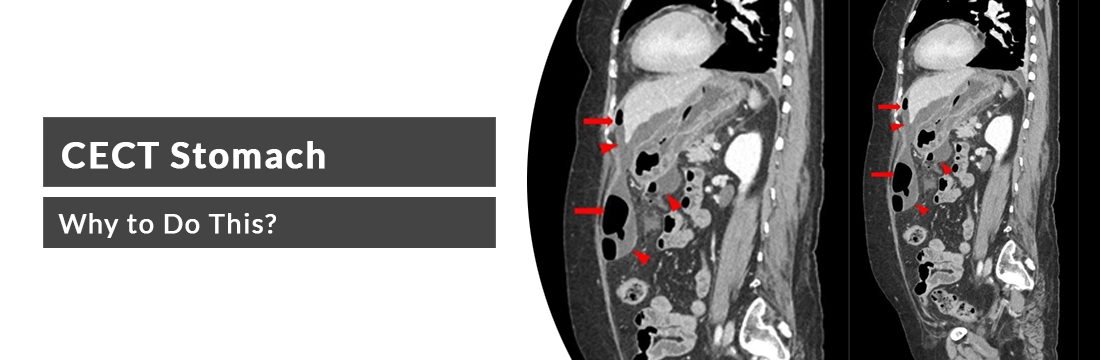

This article will elaborate on CECT stomach its need, procedure and cost..

CECT stomach is contrast-enhanced computed tomography stomach is the diagnostic tool to evaluate stomach conditions like stomach pain, appendicitis, diverticulitis, different types of cancer and tumours around the belly. In this CT, contrast is used for more clear and detailed images of the stomach abnormalities. Contrast materials like iodine-based and barium sulfate are commonly used in CECT imaging.

CECT Stomach is used to show the conditions related to stomach abnormalities. The scan uses contrast and gives the best details about the abnormalities: